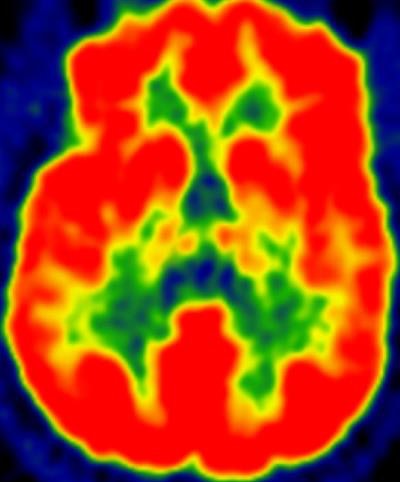

Researchers using FDG-PET have uncovered healthy patterns of glucose metabolism in the brains of people at risk for Alzheimer's disease who consistently partake in moderate-intensity physical activity, according to a study published online June 22 in the Journal of Alzheimer's Disease.

Senior author Ozioma Okonkwo, PhD, and colleagues determined that moderate physical activity, which is equivalent to a brisk walk, was associated with greater levels of glucose metabolism in all brain regions viewed on FDG-PET. In addition, subjects who spent at least 68 minutes per day engaged in moderate physical activity showed better glucose metabolism profiles than those who spent less time.